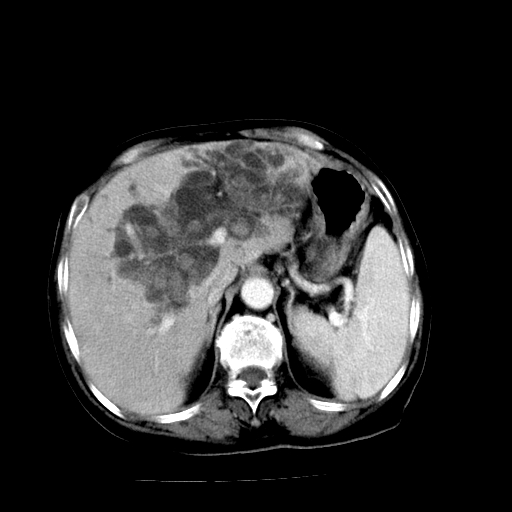

以下是引用随光逐影在2009-4-7 8:21:00的发言:[br]肝内外胆管多发性结石并肝内外胆管扩张;胆系感染。